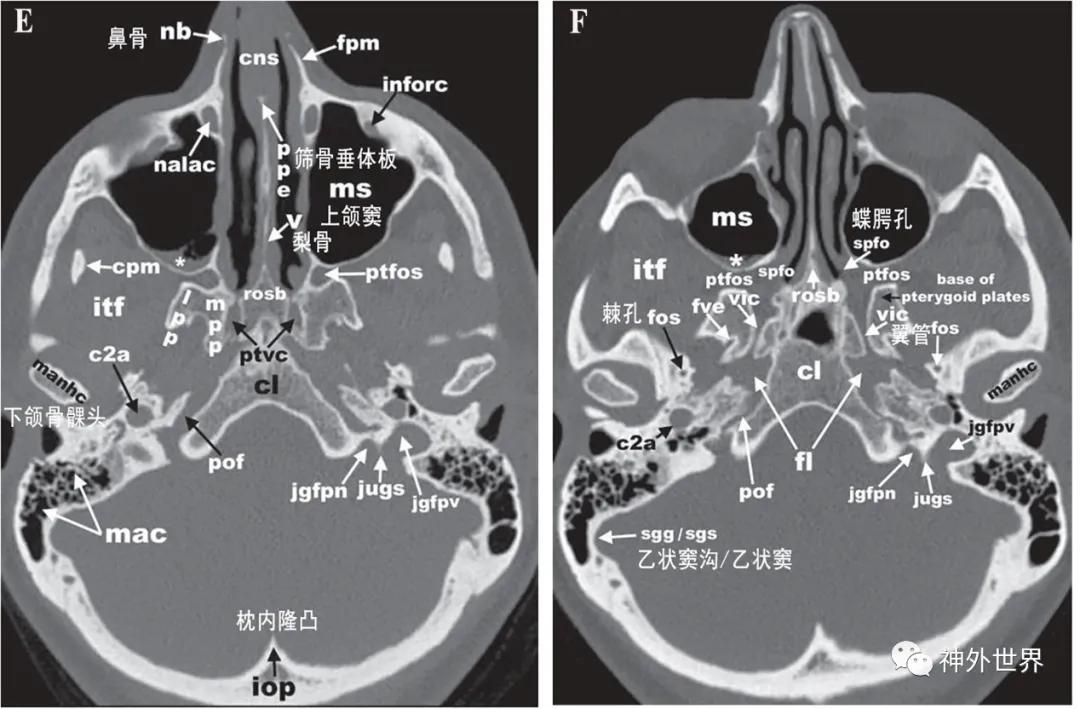

图3:颅底CT骨性横断面影像解剖

图4:颅底CT骨性冠状面影像解剖